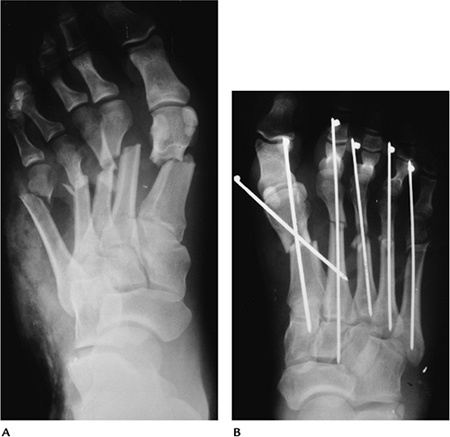

Fractures/Dislocations: Forefoot Injuries—Fifth Metatarsal Fractures

-

Fractures of the fifth metatarsal base are common in children and adults.

Fractures are categorized as proximal or distal.

Proximal fractures are divided into three zones (Fig. 6-34).

Zone 1, avulsion fractures; Zone 2, Jone’s fractures caused by forefoot

adduction; Zone 3, typically athletic stress fractures. -

Distal fractures (Dancer’s fracture) are usually the result of a direct blow.

Treatment of fractures in Zone 1 and distal fractures is conservative. Fractures in Zones 2 and 3 may require internal fixation.

Key Facts

Isolated fractures of the first metatarsal are rare.

Proximal metatarsal fractures are often associated with midfoot fracture/dislocations.

Distal metatarsal fractures usually are related to a blow from a heavy object.

Phalangeal fractures are the most common forefoot injury. Jamming or dropping a heavy object result in fracture.

Dislocations of the metatarsophalangeal

(MTP) and interphalangeal joints may occur as isolated events or be

associated with fractures.-

The first MTP and proximal interphalangeal joints are most commonly dislocated.

![]() |

|

FIGURE 6-36 Crush injury. (A) AP radiograph demonstrates complex comminuted metatarsal fractures. (B) Fractures were reduced using K-wire fixation.